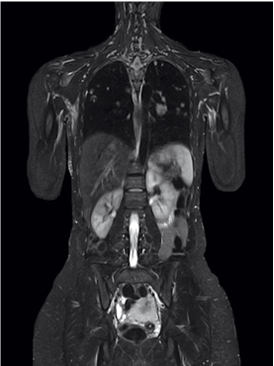

MRI:

The Siemens MRI machine is the latest multi-channel multi-transmitter machine.

- Its ultra-fast image acquisition results in shorter-than-ever examination times, scanning any body part in 7-8 minutes in very high resolution

Seamlessly scanning up to 205 cm with no patient repositioning or coil changes